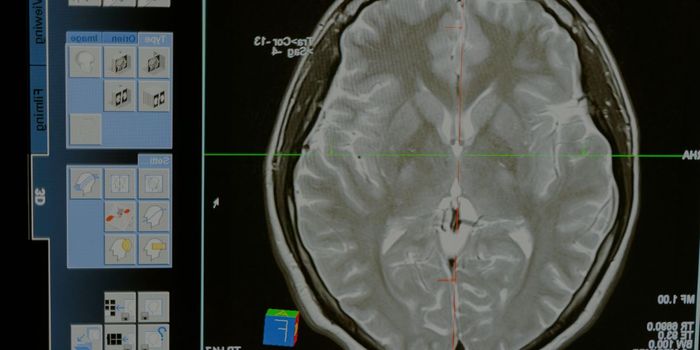

DEC 03, 2024Clinical & Molecular DXMRI (magnetic resonance imaging) is an incredible technique that was developed in the 1980s. It uses radio waves, giant ...